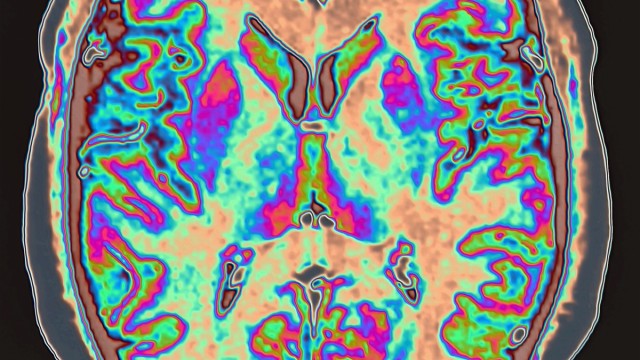

The Brain and Behaviour section in the School of Psychology brings together a number of research labs and researchers that investigate the neurocognitive basis of human behaviour across the lifespan in both non-clinical and clinical populations.